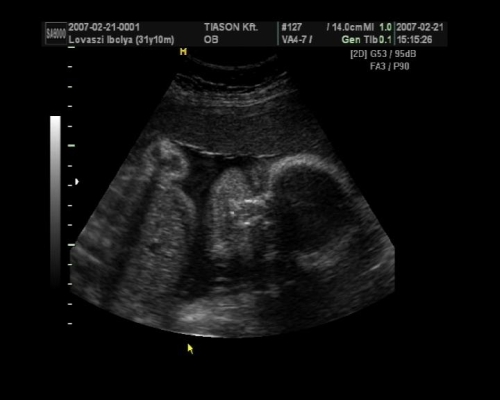

, de ami fura volt, a szívét a pocakom bal oldalán középtájban éreztem, felette pedig folyamatos rugdosást, vagy kalimpálást, De a másik oldalon ugyanott szintén... Lehet, hogy keresztben van???? De a múltkor már lent volt. Na kíváncsi vagyok kedden mit mutat az UH. Dehát azt csak lehetne látni rajtam, ha keresztben lenne...